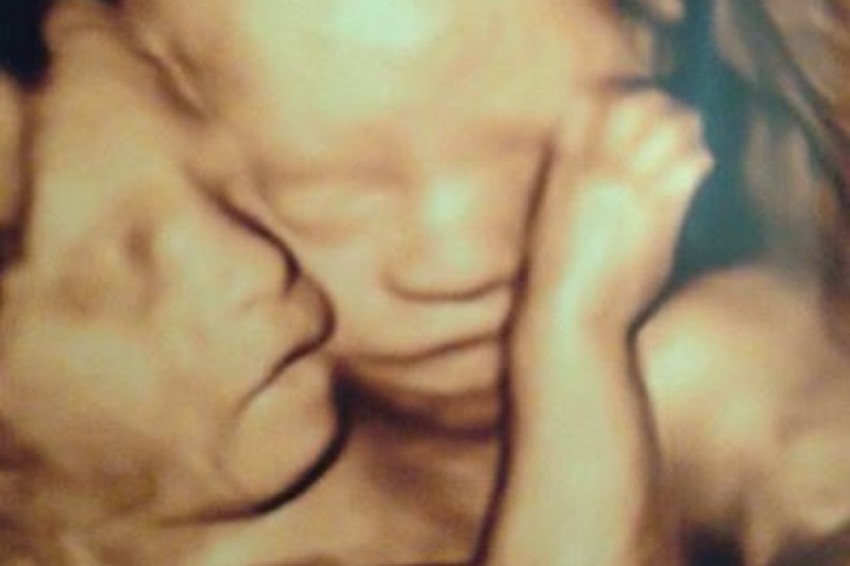

A Hastings, Minnesota, woman who gave birth to conjoined twin girls last week but is now grieving the loss of one which died during an operation to separate the sisters, is also giving thanks to God through her heartbreak. Amber McCullough, a 31-year-old U.S. Army Reserves captain and attorney, gave birth to Hannah and Olivia via Cesarean section at just 32 weeks into her pregnancy at Children's Hospital Colorado.

When doctors initially told McCullough that her girls were conjoined twins — a rare condition that occurs just once every 200,000 births, according to the University of Maryland Medical Center — they said there was a high chance they could be stillborn. Although the girls shared an abdomen, liver and intestinal tract, Olivia had an especially low chance of survival because her heart had only one ventricle, and she had only one leg and a congenital brain malformation.